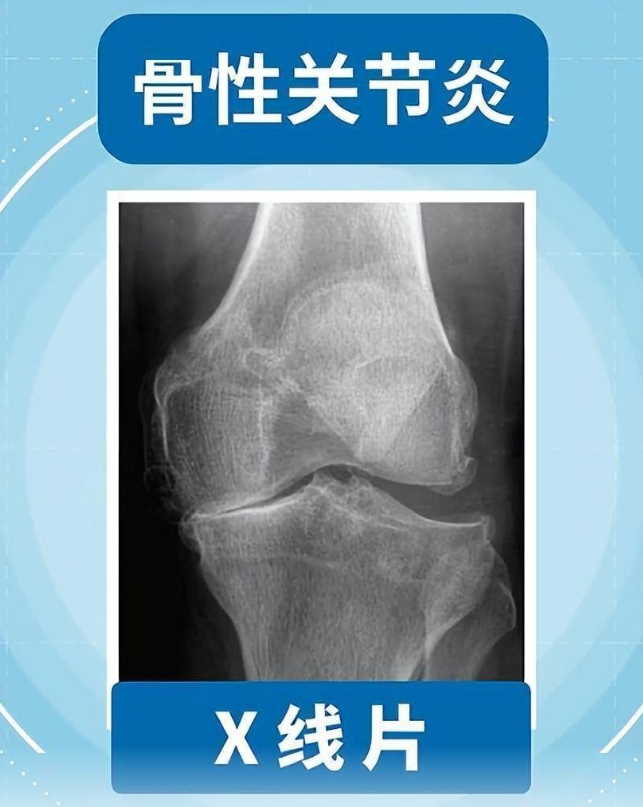

1点资讯网页版:且行且珍“膝”!膝盖脆弱的你,请收好这份护“膝”秘籍